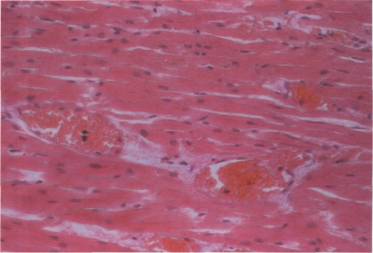

Рис.

1. Периваскулярный и перицеллюлярный отек, очаговое разряжение ткани головного

мозга. Окраска гематоксилин-эозином.

Микроскопическая

картина головного мозга характеризуется неравномерным кровенаполнением,

множественными фибриновыми тромбами в сосудах микроциркуляции, плазматическим

пропитыванием и фибринойдным некрозом стенок артериол, периваскулярным и

перицеллюлярным отёком, очаговыми некрозами (Рис.1). Полученные

патоморфологические данные совпадают и с результатами магнитно-резонансной

томографии головного мозга, свидетельствующими о грубых нарушениях

кровообращения в затылочно-теменных областях и отсутствии грубого отека

головного мозга в остром периоде развития преэклампсии и эклампсии.